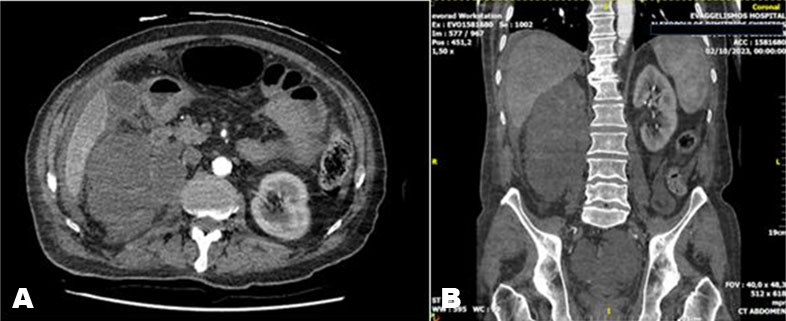

Inguinal hernia is a very common pathology worldwide. Global incidence is about 4–5%. The most commonly involved organs are the abdominal viscera. As far as urology is concerned, urinary bladder is involved in approximately 0.5–4% of all inguinal hernias, while finding the ureters is truly a rarity, about 150 cases worldwide. Ureteral hernias could be an incidental finding but it is important to know about their existence to avoid injury during surgery. We present the case of a 71-year-old man with a finding of right ureteral hernia incidentally diagnosed during computed tomography (CT) scan for an abdominal abscess.